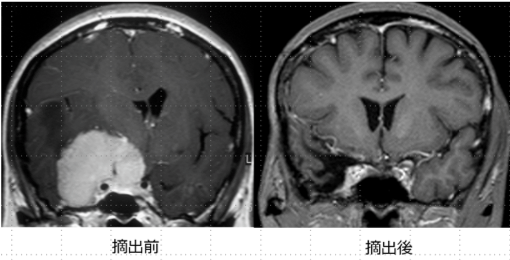

プロラクチン産生腺腫(プロラクチノーマ)を除く下垂体腺腫に対しては、基本的に内視鏡下経鼻的下垂体腫瘍摘出術を行います。当施設では、最新の内視鏡手術装置および手術用ナビゲーションを常備しており、狭い術野でも安全かつ確実に手術を行うことが可能です。最近では高齢の患者さんも増えており、手術前には内科や麻酔科とも十分相談し耐術能についてもきちんと評価した上で手術を受けていただきます。この手術では、鼻孔から内視鏡を挿入し、蝶形骨洞(副鼻腔の一部)を経由してトルコ鞍という腫瘍が収まっている頭蓋骨のくぼみに到達します。この骨に1.0〜1.5cm程度の小さな穴を開け、正常下垂体や周囲の重要な血管(海綿静脈洞や内頚動脈など)を傷つけないようにしながら腫瘍を最大限に摘出します。摘出後の空洞には、通常右下腹部から採取した脂肪片を埋めた後、手術用の接着剤(フィブリン糊)でしっかりと固定します。最後に鼻腔内をタンポンガーゼでパッキングします。この方法は、脳を直接触らないため比較的安全な手術と考えますが、髄液漏、尿崩症や鼻出血などの合併症があります。

尚、手術を受けていただく際は、可能な限り外来段階で術前検査を行うことにより、術前2-3日前に入院、術後10日間程度で退院できるようにしています。